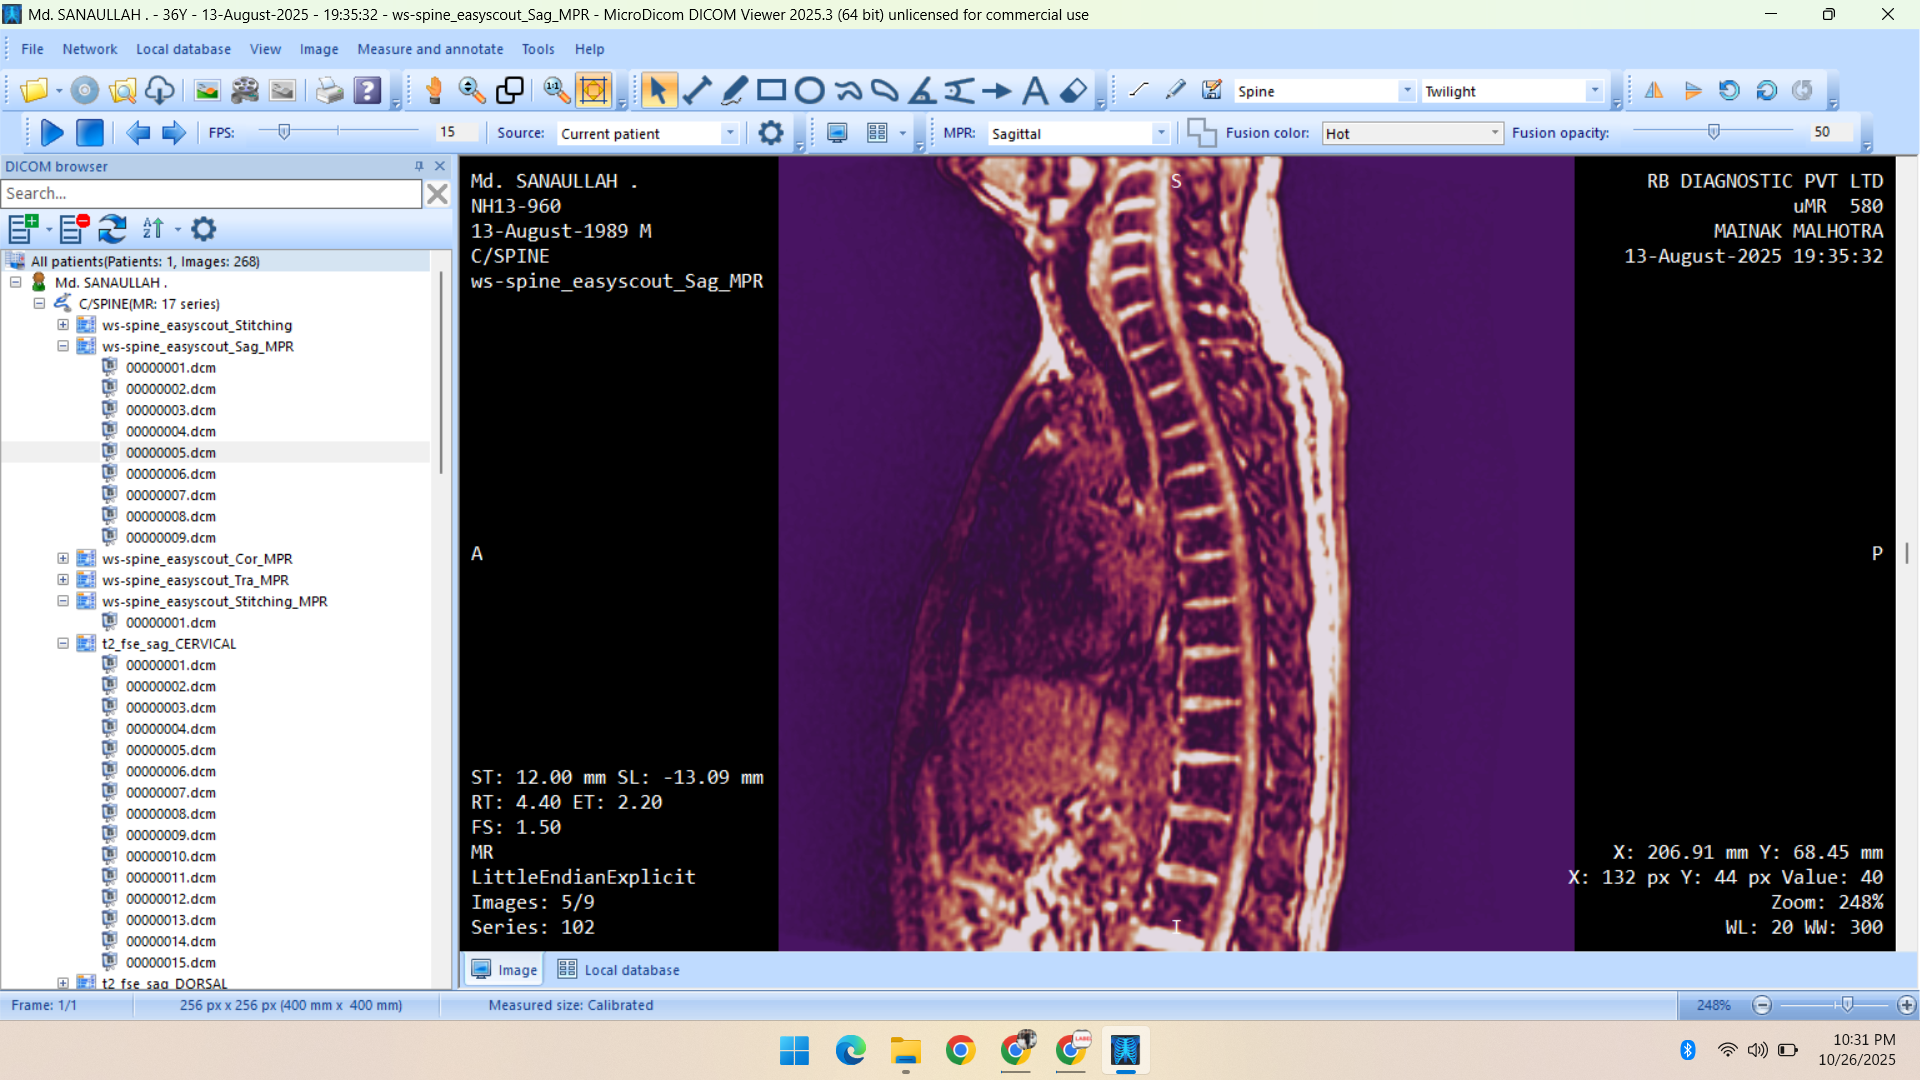

- Radiology Data – CT Scans, X-Rays, MRI, Echocardiography, Ultrasound.

Healthcare & Medical Data Supply

We specialize in healthcare datasets including radiology (CT, X-ray, MRI, Ultrasound, Echocardiography), pathology microscopy, and histopathology images — all ethically sourced and research-ready.

Portfolio

Showcasing Innovative AI Solutions and Data Services: Delivering Quality Data for Smarter, Future-Ready Applications

- MRI